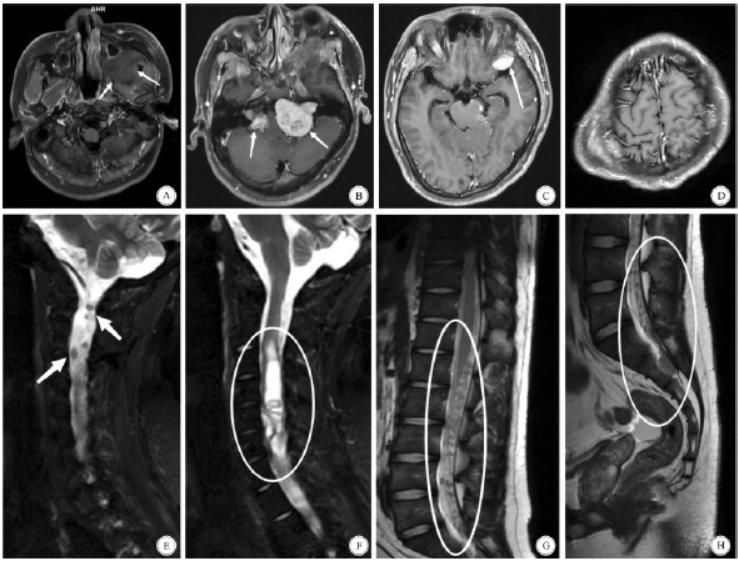

影像学检查提示患者颅内、翼腭窝、头皮下、颈、胸、腰及骶尾部散在占位(图1)。患者行3 次手术依次切除了左侧听神经瘤、左侧颞窝脑膜瘤、左侧翼腭窝区神经鞘瘤、C2 - 7髓内室管膜瘤、颈椎椎管内髓外神经鞘瘤及右侧颞顶枕部皮下神经鞘瘤(图2、图3)。术后病理结果显示左侧桥小脑角区、左侧翼腭窝、右侧颞顶枕部头皮下及颈椎管内髓外的肿瘤为神经鞘瘤,左侧颞窝肿瘤为脑膜瘤,颈椎管内髓内肿瘤为室管膜瘤。

图1 患者的术前影像学资料。A:MRI T1 提示患者左侧颞下、翼腭窝占位; B:MRI T1 增强提示患者双侧桥小脑角区占位,以左侧为主,脑干及第四脑室严重受压; C:MRI T1 增强提示患者左侧颞窝占位; D:CT 提示患者右侧颞顶枕部皮下占位; E:MRI T2 提示患者颈椎椎管内髓外多发占位; F:MRI T2提示患者颈髓内占位; G、H:MRI T1 提示患者腰、骶多发占位